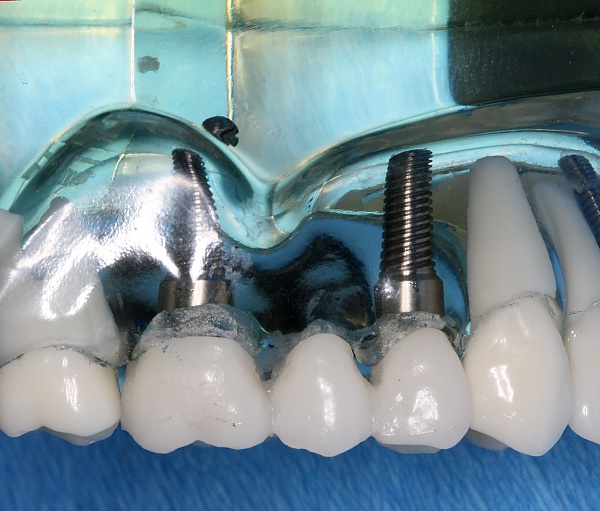

Конструкция

По виду конструкции различают разборные и неразборные (однокомпонентные) имплантаты.

Разборный имплантат состоит из непосредственно имплантата и надстройки (супраструктуры), именуемой абатментом. Такой имплантат может быть установлен по одно- и двухэтапному протоколу. Двухэтапный протокол подразумевает полное погружение имплантата и накрывание его слизистой оболочкой, в результате чего исключается любой контакт имплантата с полостью рта — эта процедура называется первым этапом дентальной имплантации. Второй этап заключается в установке какой-либо надстройки (супраструктуры) — это может быть как формирователь десны, так и абатмент с временной коронкой или другим видом протезной конструкции. После какого промежутка времени будет выполнен второй этап обычно решает имплантолог, опираясь на данные о качестве костной ткани, возраст и общее состояние пациента, а также свой клинический опыт. Классические сроки составляют 4—6 месяцев, однако последнее время существует тенденция к сокращению сроков ожидания до 2,5—3 месяцев. Это связано с лучшим пониманием процесса остеоинтеграции, а также оптимизацией макродизайна и микрохарактеристик поверхности имплантатов.

В неразборном имплантате (употребляются также термины: одноэтапный имплантат, моноимплантат) внутрикостная часть имплантата и абатмент обычно изготовлены из единого куска материала. После установки имплантат своей наддесневой частью сразу оказываются в контакте с полостью рта. На усмотрение доктора устанавливается формирователь десны либо временная коронка. В случае установки временной протезной конструкции (коронки, моста или полного протеза) на имплантат не позднее трёх дней после имплантации говорят о немедленной нагрузке.

Под термином «имплантация зубов» в стоматологии понимают только вживление зубного имплантата. В дальнейшем на вживлённый имплантат с помощью цемента крепится коронка, которая может быть временной — пластмассовой, металлокерамической, керамической, золотой и т. д. Относительно кости она должна располагаться на том же уровне, на котором ранее располагалась коронка зуба, замещаемого имплантатом. В практике чаще всего применяются два вида фиксации коронок на имплантаты: цементная или винтовая.